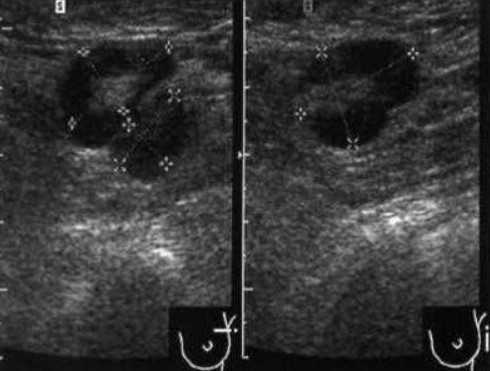

Метастазы рака молочной железы в поверхностных лимфоузлах

УЗИ подмышечных лимфоузлов

УЗИ аксиллярных лимфоузлов

Диагностический поиск при увеличении ЛУ в подмышечных впадинах направлен и на выявление онкологических заболеваний, преимущественно рака молочной железы.